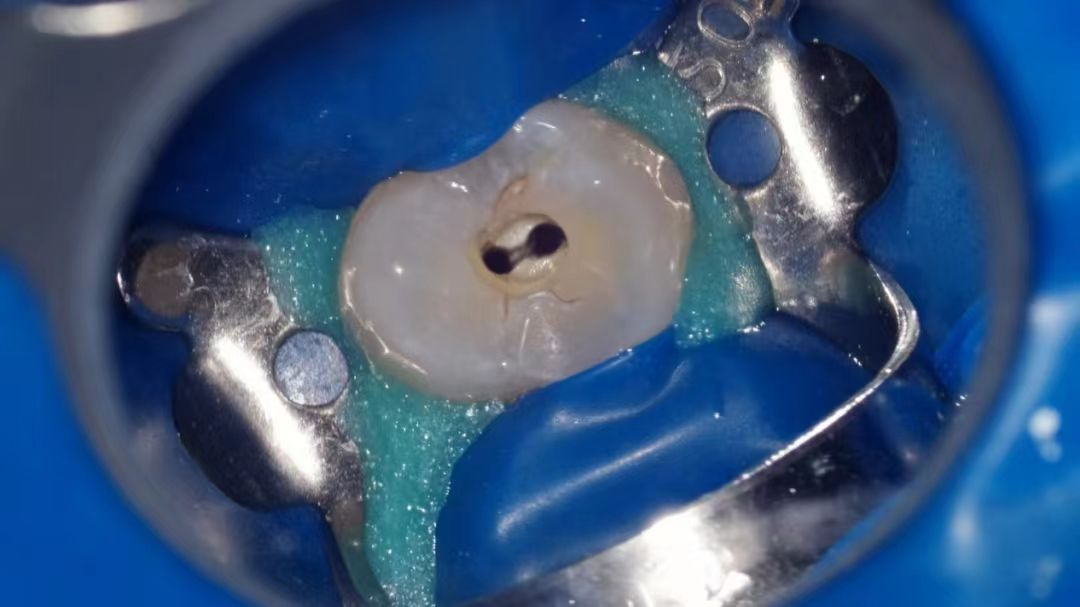

显微镜辅助下根管预备